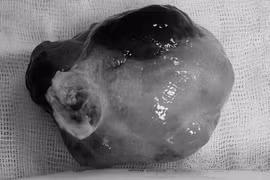

Một bệnh nhân nam 34 tuổi ở Nghệ An mang khối u “khủng“ nặng tới 45 kg đã được các bác sĩ Bệnh viện Việt Đức phẫu thuật cắt bỏ sau hàng chục năm gù lưng cõng khối u.